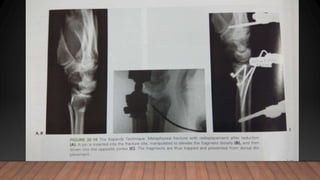

TECHNIQUE OF REDUCTION

• Agee technique :a volar transition force is applied to the distal fragment of

PERCUTANEOUS PINNING

reduction tools and then driven into the proximal radius

INTRAFOCAL PINNING

• Pins are driven into the fracture site and used as levers to reduce the fracture

• KAPANDJI recommends 3 wires placed laterally , posterolaterally and

posteromedially

• A small vertical incision is made at the fracture site

• On the radial side, pin is inserted in the plane between tendons of extensor

pollicis breves, abductor pollicis longus and wrist extensors

• Posterolateral incision: just above and lateral to lister’s tubercle ; pin is placed

b/w the tendons of EPL and tendons of EPB & APL

• Posteromedial incision: in the 4 th extensor compartment , usually b/w the

extensors of the ring and little finger

• Pins are introduced perpendicularly in the line of fracture and then inclined

obliquely upwards thus buttressing cortex of the distal fragment.

• The pin is then driven into the opposite cortex of the radius